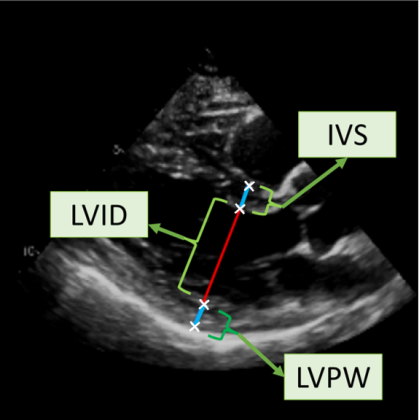

![]() |

|

| (a) LV Measurements | (b) Label Smoothing |

Left Ventricular Hypertrophy (LVH), one of the leading predictors of adverse cardiovascular outcomes, is the condition where heart’s mass abnormally increases secondary to anatomical changes in the Left Ventricle (LV) [10]. These anatomical changes include an increase in the septal and LV wall thickness, and the enlargement of the LV chamber. More specifically, Inter-Ventricular Septal (IVS), LV Posterior Wall (LVPW) and LV Internal Diameter (LVID) are assessed to investigate LVH and the risk of heart failure [21]. As shown in Figure 1 (a), four landmarks on a parasternal long axis (PLAX) echo frame can characterize IVS, LVPW and LVID, and allow cardiac function assessment. To automate this, machine learning-based (ML) landmark detection methods have gained traction.

It is difficult for such ML models to achieve high accuracy due to the sparsity of positive training signals (four or six) pertaining to the correct pixel locations. In an attempt to address this, previous works use 2D Gaussian distributions to smooth the ground truth landmarks of the LV [9, 13, 18]. However, as shown in Figure 1 (b), for LV landmark detection where landmarks are located at the wall boundaries (as illustrated by the dashed line), we argue that an isotropic Gaussian label smoothing approach confuses the model by being agnostic to the structural information of the echo frame and penalizing the model similarly whether the predictions are perpendicular or along the LV walls.